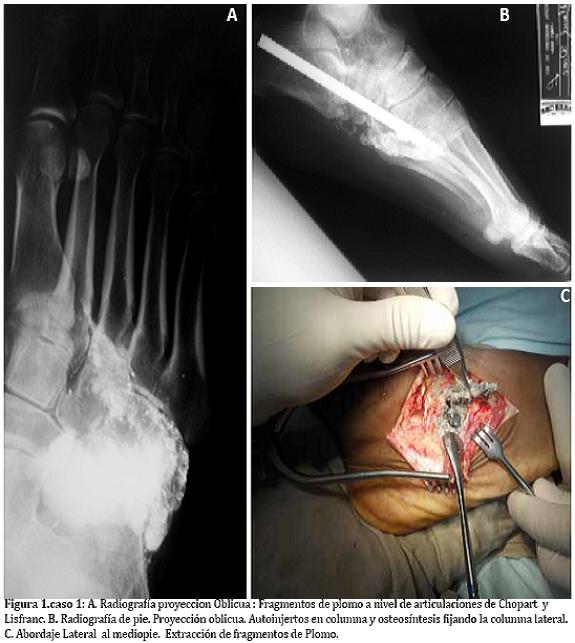

Paciente masculino de 38 anos, cuadro de 3 años de evolución de dolor abdominal paroxístico, emesis postprandial y pérdida de peso. Manejo medico con mejoría parcial del cuadro. Progresa con exacerbación de los síntomas, comportamiento bizarro, agresividad y convulsiones. Antecedente hace 15 anos de herida por arma de fuego en pie. Tabaquismo y alcoholismo hasta la embriaguez. Al exámen físico con disminución de la fuerza muscular de predominio niveles medulares C5 - T1. Hiporeflexia aquiliana. El cuadro hemático y frotis de sangre periférica evidencian anemia microcítica hipocrómica. Niveles de Plomo: 90.3 µg/dl. Radiografía de pie con evidencia de múltiples fragmentos metálicos a nivel de articulaciones del mediopié. Artrosis de articulaciones Calcáneo-cuboidea , Talo-navicular y subtalar (Figura 2A).

Se hace el diagnóstico de Saturnismo, inicio de terapia Quelante con EDTA (50 mg/Kg/día) por 7 días. Es llevado a cirugía para extracción de los proyectiles alojados en pie y artrodesis del retropié. (Figuras 2B-D).